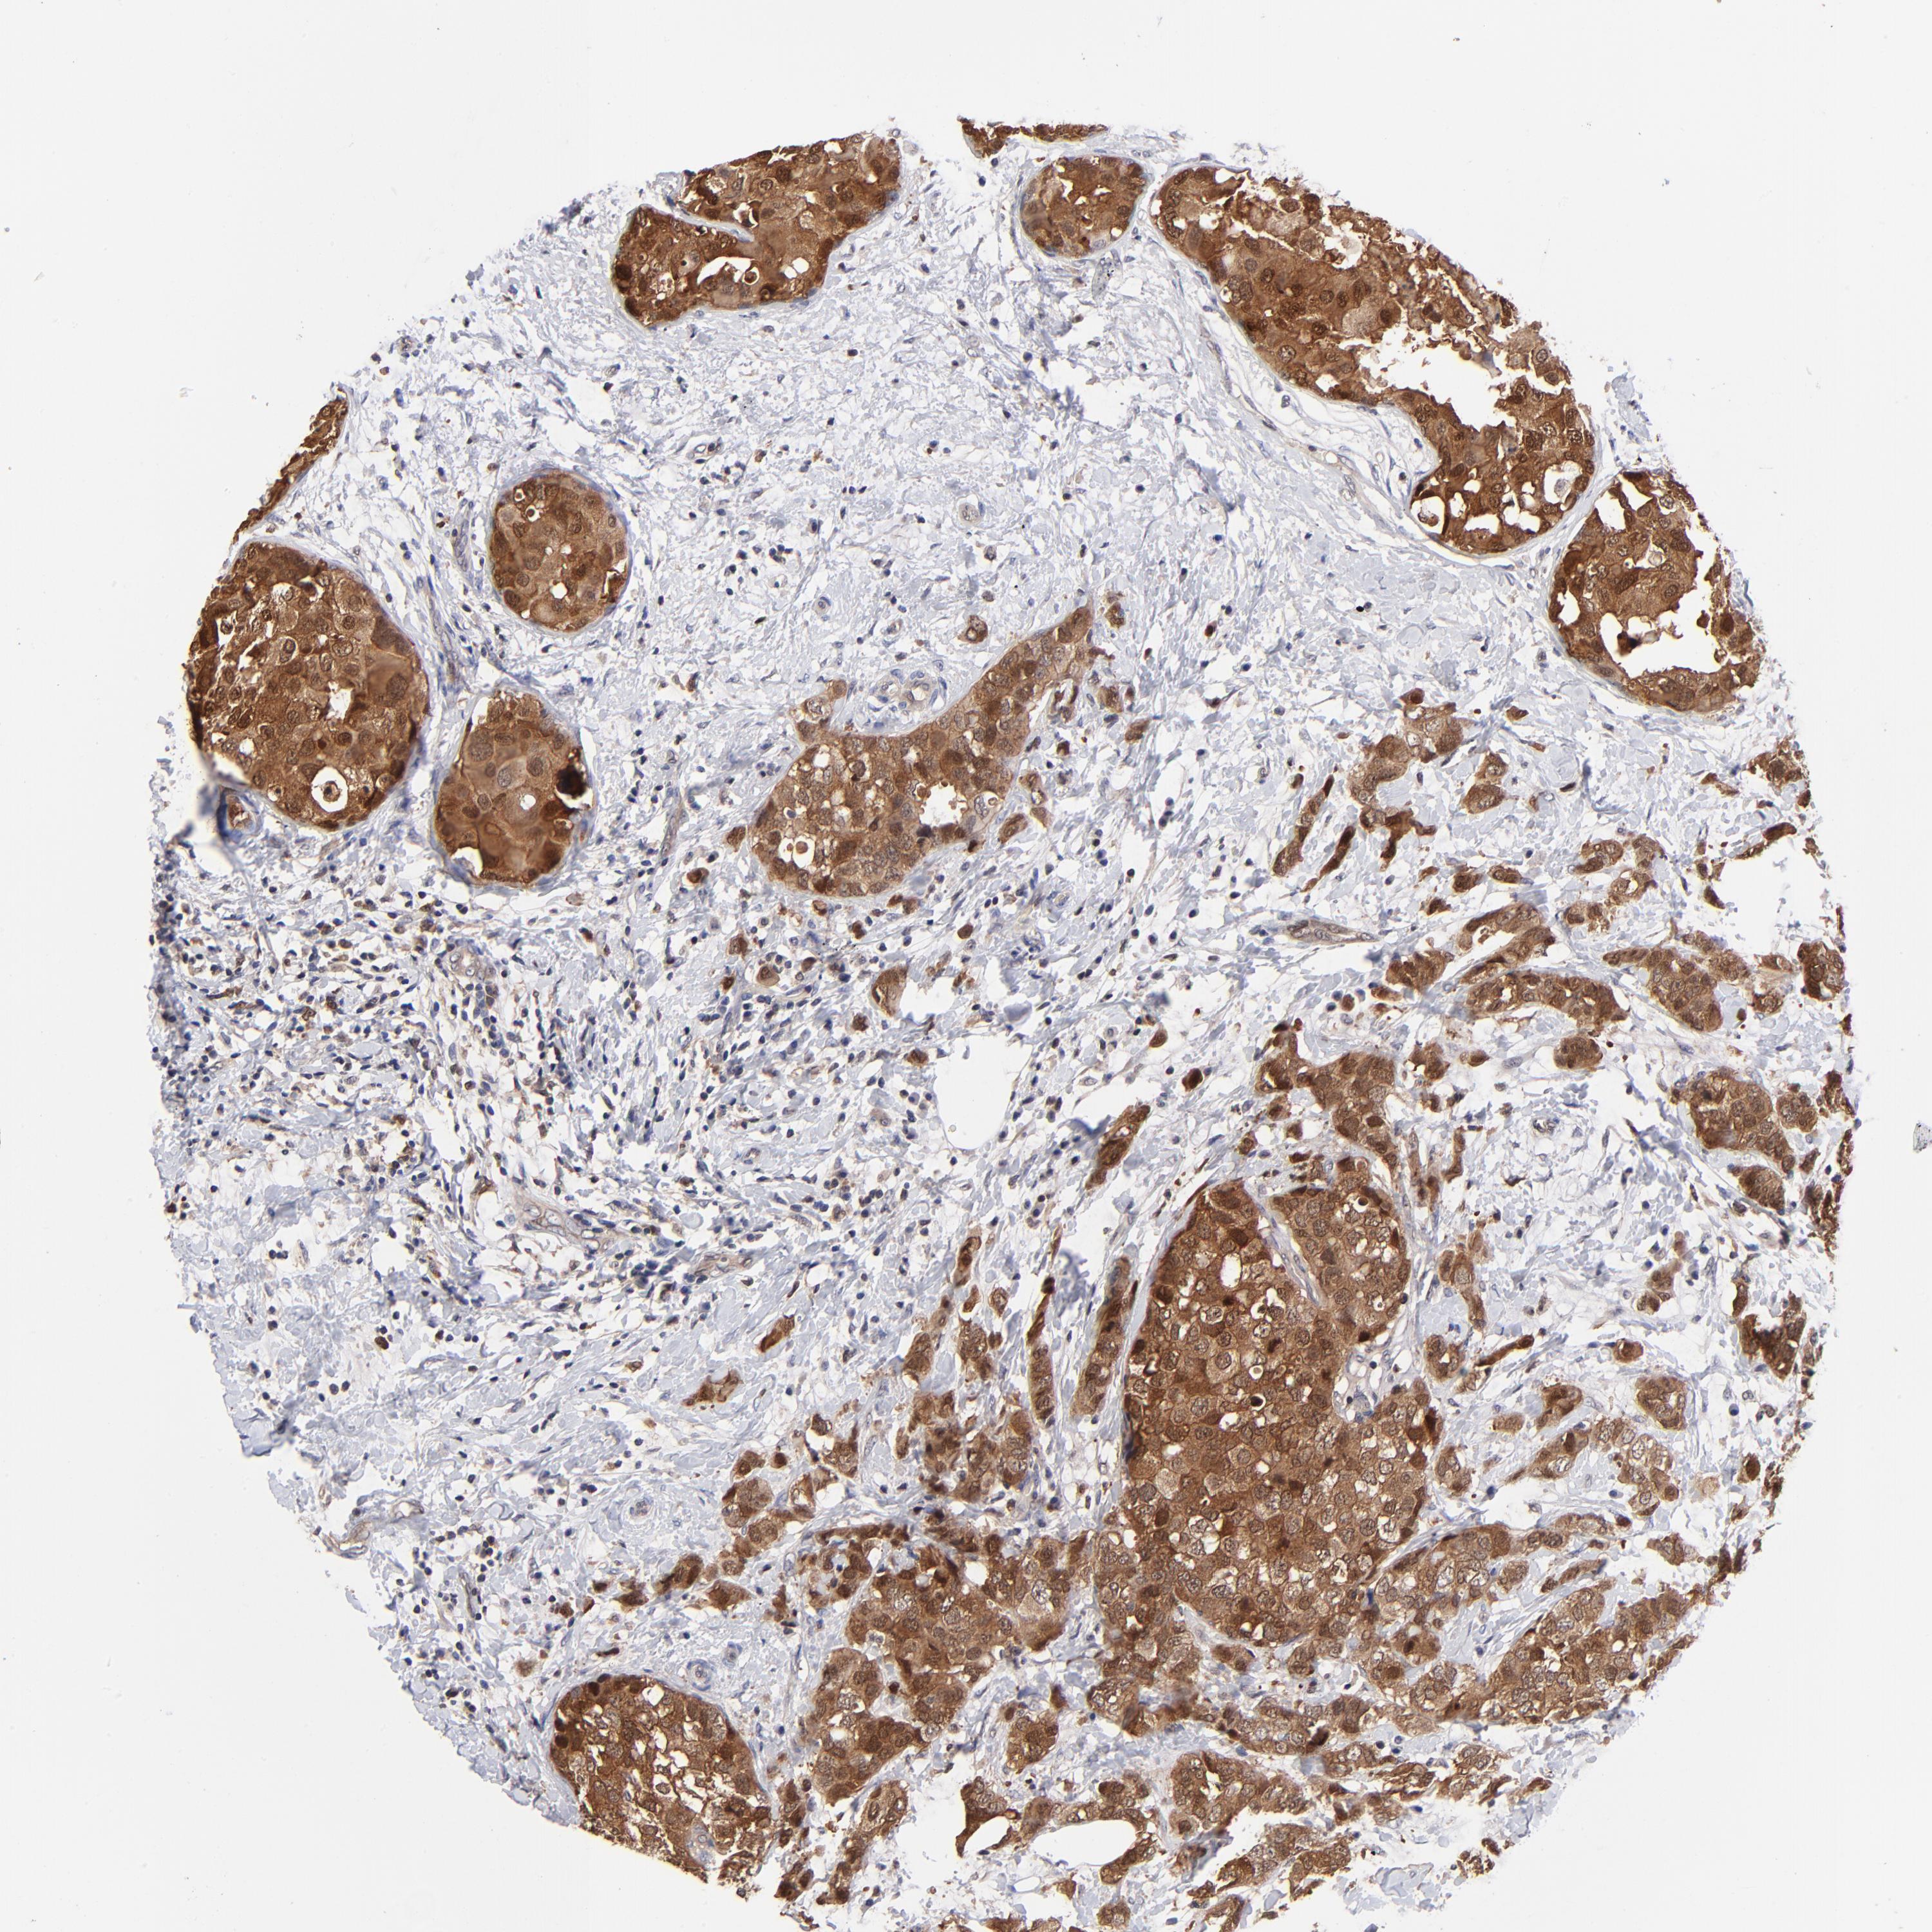

BRCA TCGA BRCA VALIDATION PROTEIN EXPRESSION

ANTIBODIES

AND

VALIDATION